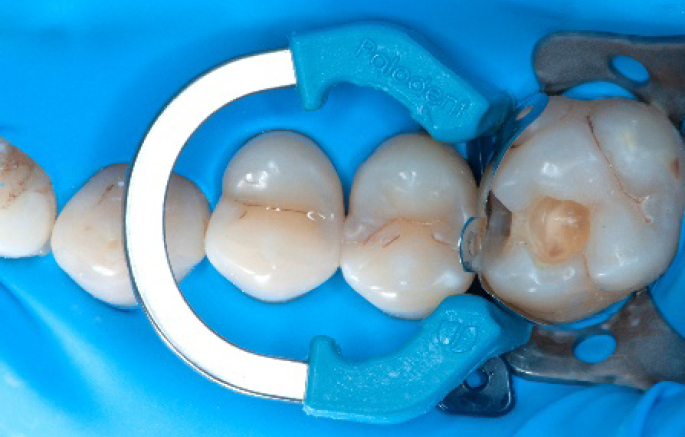

Step 1:

The situation after rubber dam isolation.

Step 2:

Initial cavity preparation, protecting the adjacent tooth with a Palodent1 WedgeGuard.

Step 4:

The complete Palodent1 system in place: sectional matrix, wedge and ring.